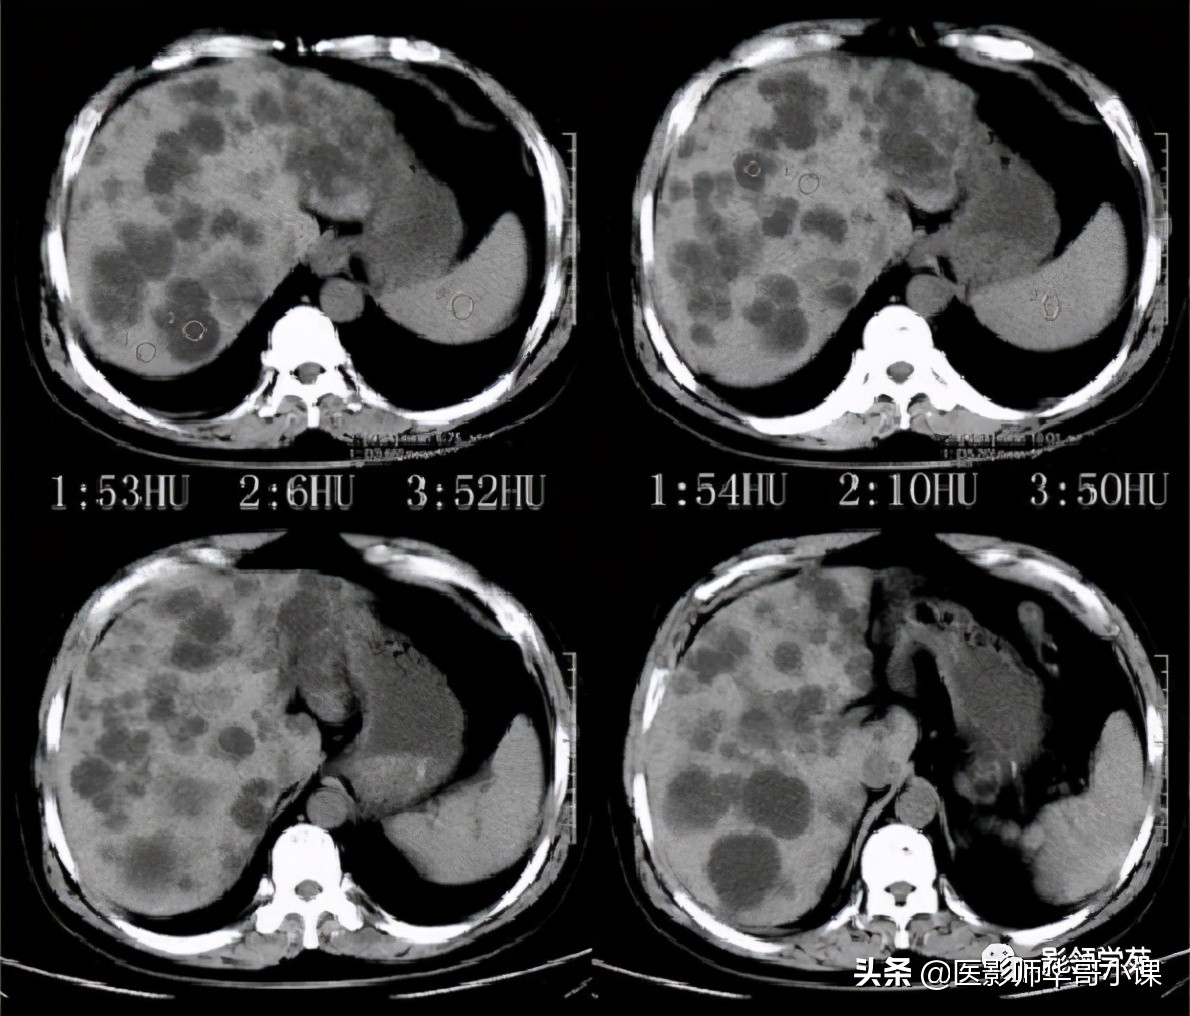

- 部分囊状扩张的胆管腔内有门静脉分支(箭头)

Caroli病影像诊断要点

1、肝内胆管不成比例的扩张,并与正常胆管相间,这是鉴别本病与继发性阻塞性肝内胆管扩张的关键所在,后者表现为从中央向末梢逐渐变细的、成比例的扩张。

2、“中心点征”是又一重要的征象,是指囊肿阴影内的小点状软组织影像,平扫密度等于或高肝实质,在T2WI序列上呈环状低黑信号,中央区呈圆柱稍高信号,其病理基础是门静脉分支被胆管扩张的囊壁包绕,并在切面上呈轴位投影。Seth等认为“中心点”征象的出现足准确的诊断本病。